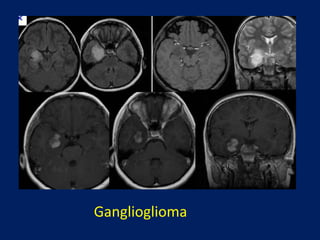

Ganglioglioma